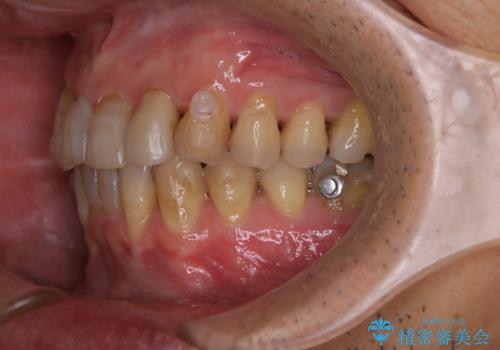

数年ぶりに歯のクリーニング(PMTC)